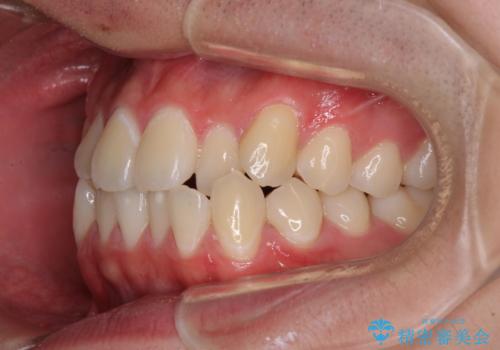

受け口傾向の咬み合わせ インビザラインできれいな口元に

- 前歯のデコボコを治したいとのことで来院された患者様です。

受け口傾向の骨格であり、前歯はクロスバイトまたは切端咬合となっており、叢生は警備であったため、下顎を中心に歯列全体の後方移動を行い、IPR(歯と歯の間を削る)によってデコボコが解消するように設計し、インビザラインにより治療を行うこととしました。

受け口傾向のインビザライン矯正は比較的治療を行いやすいため、きれいに仕上げることができました。舌の突出癖が顕著であったため、改善のためのトレーニングをしっかりと行っていただきました。